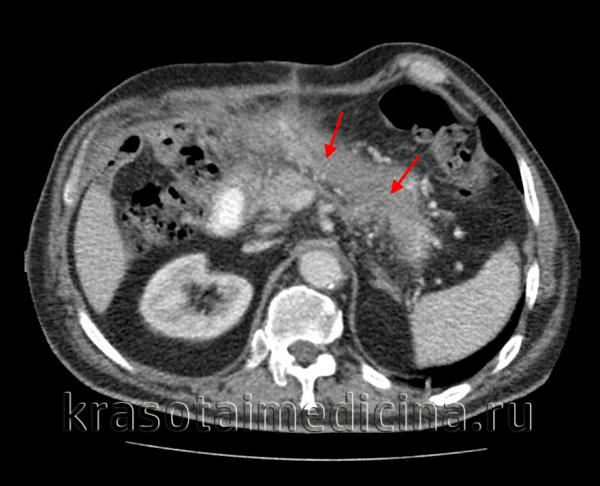

(Правый) У этого же пациента при КТ с контрастным усилением на поперечной томограмме наблюдается полное отсутствие контрастирования тела и хвоста поджелудочной железы, что характерно для панкреонекроза. Также определяется пери панкреатическое скопление жидкости, содержащее нежидкостные фрагменты, это указывает на острый некроз перипанкреатических тканей и формирование очага острого некроза.

(Правый) У того же пациента при КТ с контрастным усилением на поперечной томограмме большая часть поджелудочной железы не контрастируется, что указывает на развитие некроза; в хвосте железы определяется остаточная жизнеспособная ткань. Граница между передним краем поджелудочной железы и очагом острого некроза различима с трудом.